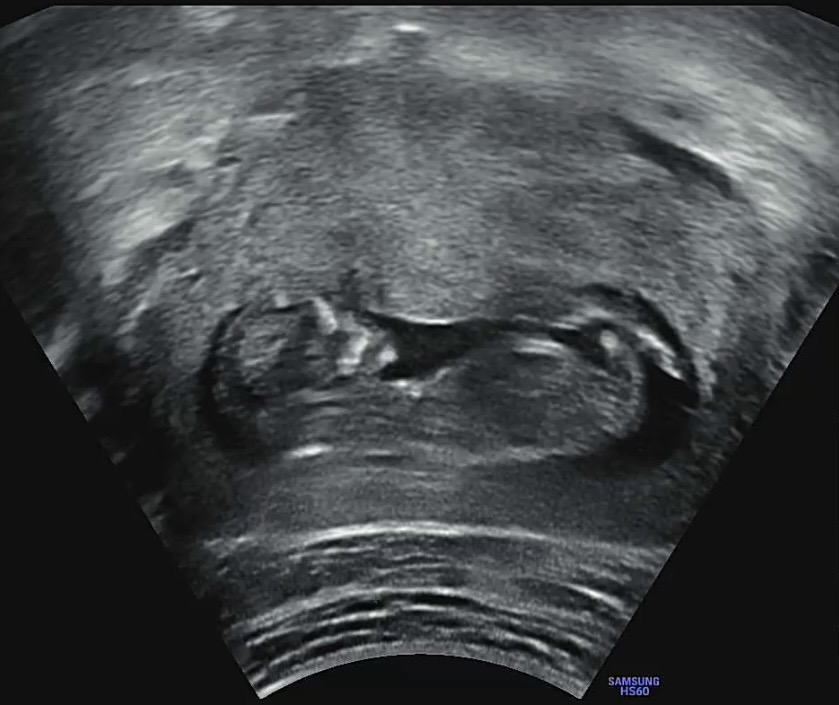

각도법봐주세요(12주차3일)

아들인가요...???? 딸이길 바라지만 🥹 뭐아무렴 상관없죠

아들일꺼 같긴해용... 정확하진 않아요!

조끔 이른거 같아요ㅠㅠ 보기가 좀 애매 하달까요..? 13주 이후에 다시 올려보세용~